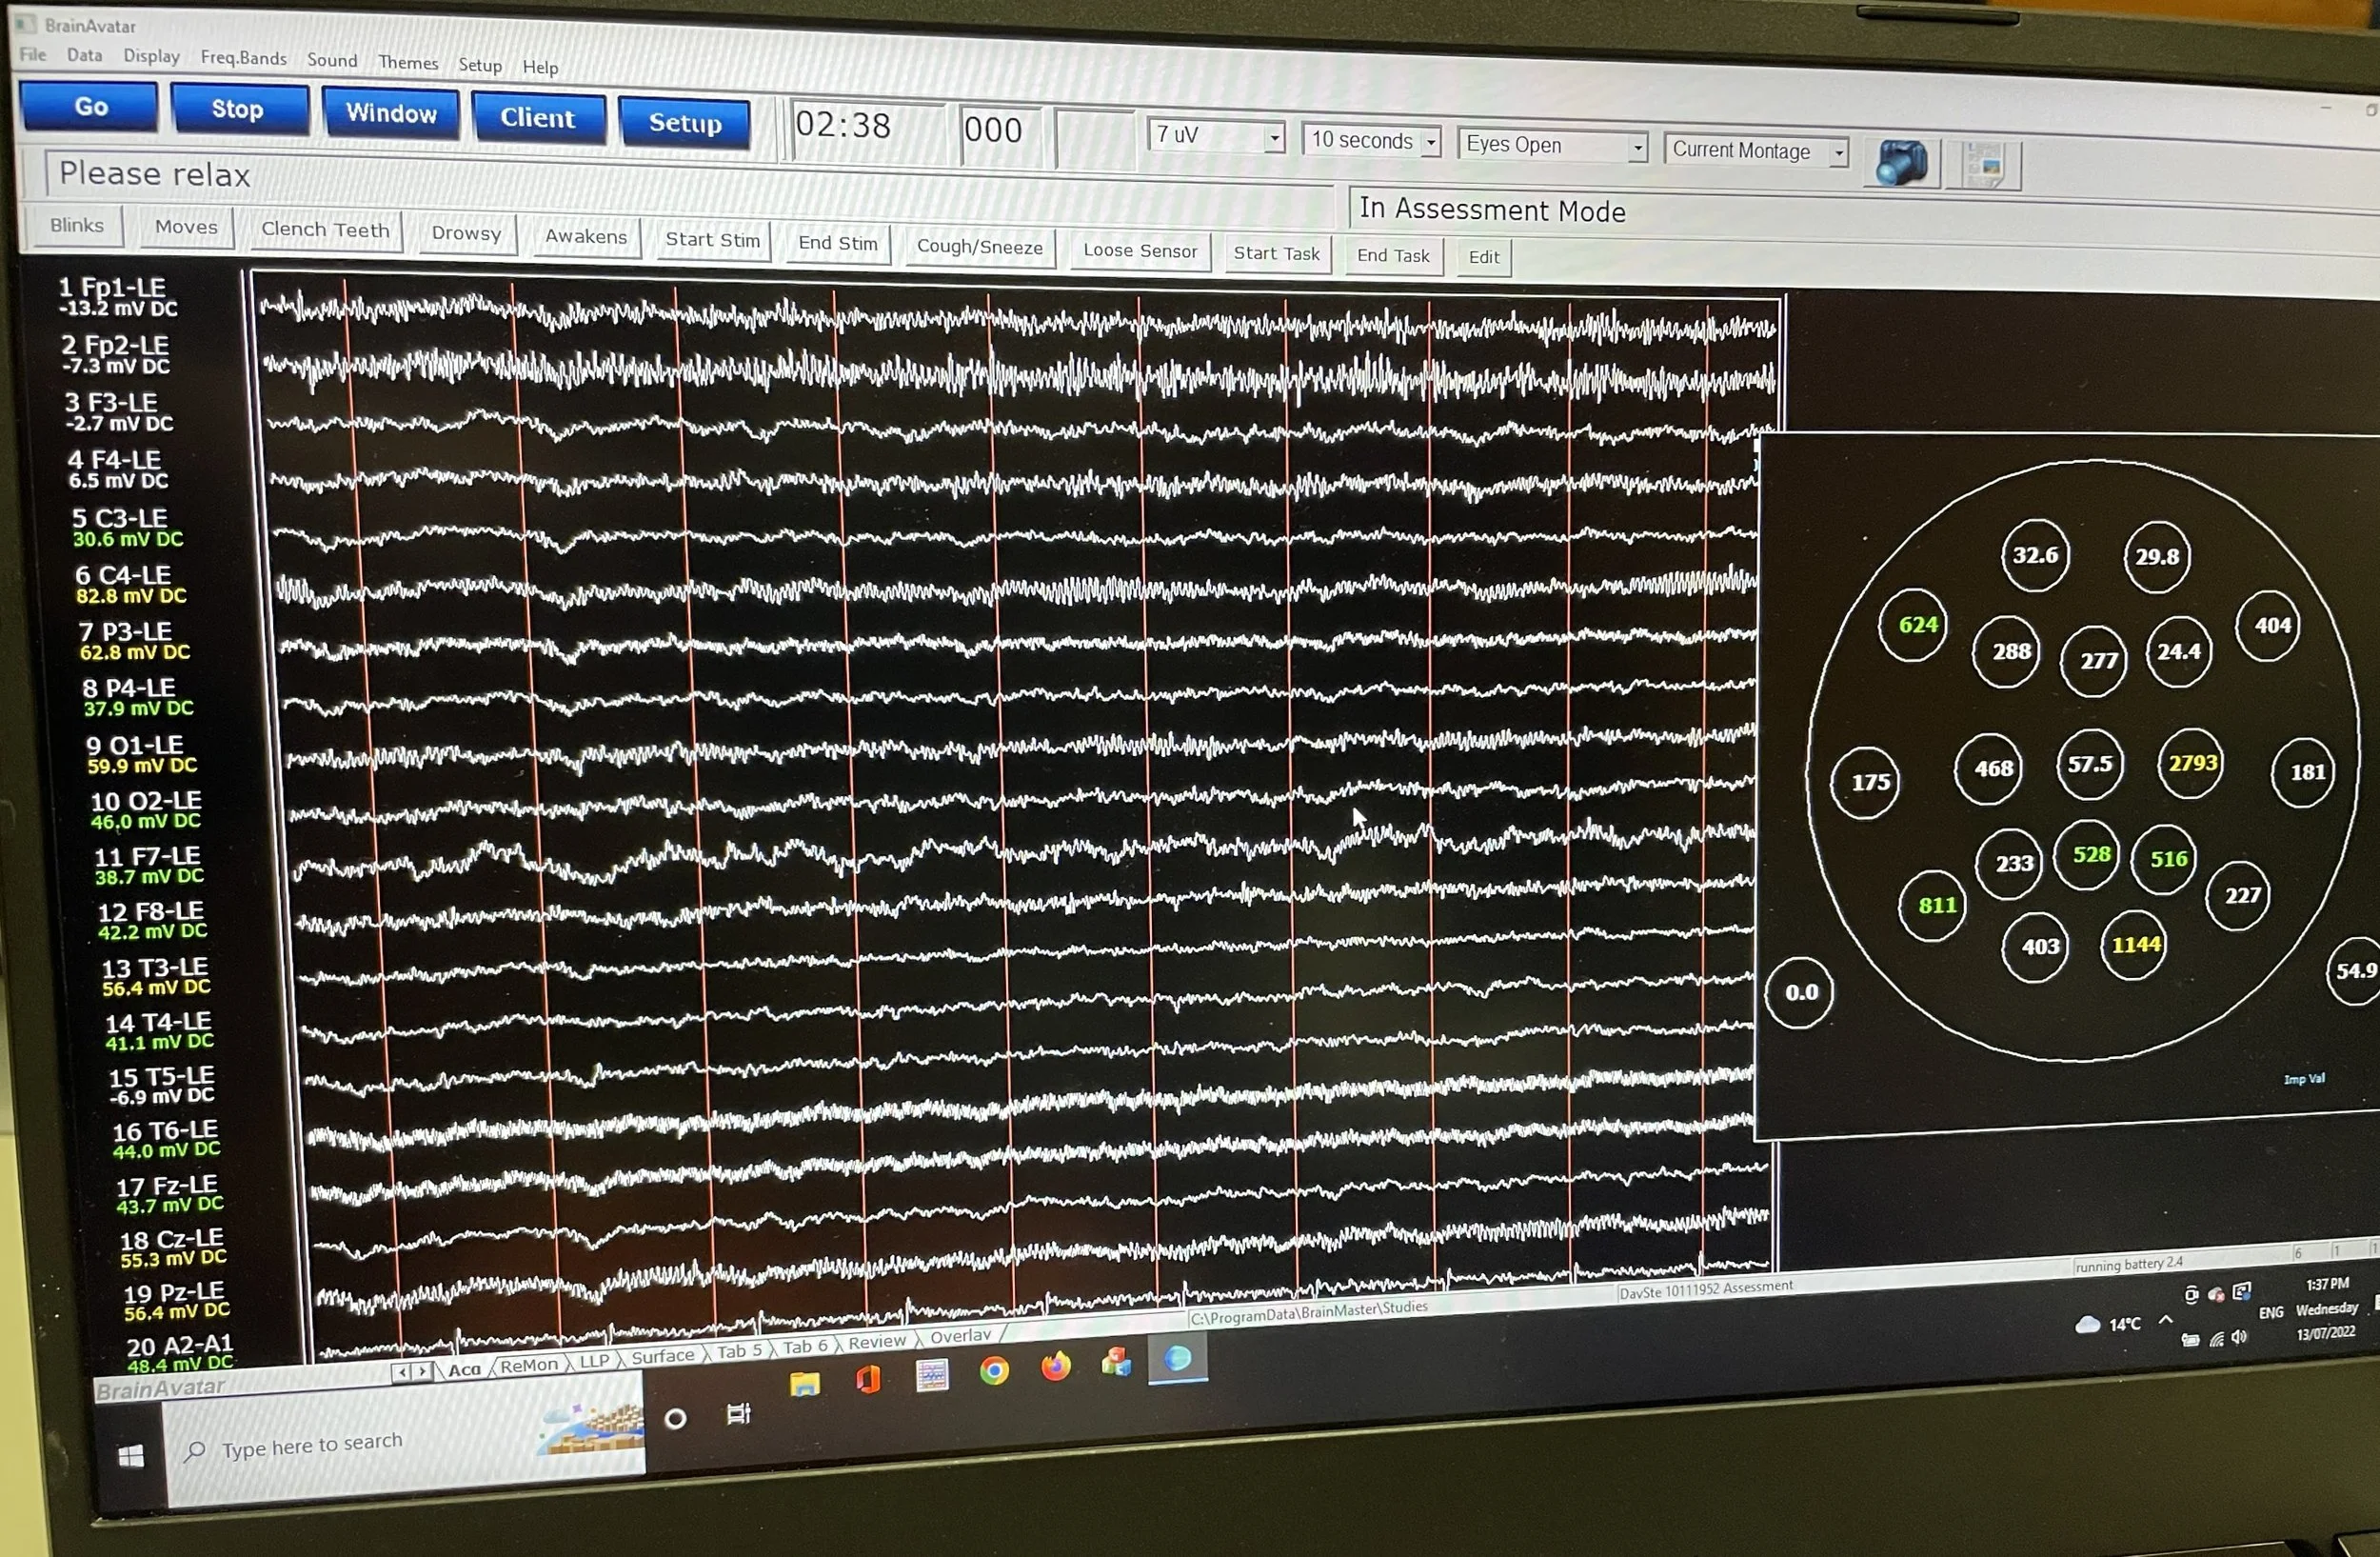

Quantitative Electroencephalography (QEEG), specifically the 19-channel variant, represents a significant advancement in the field of brain wave analysis and neurofeedback for clinicians. Traditional EEG (electroencephalography) records the electrical activity of the brain through electrodes placed on the scalp, providing invaluable data about brain function and pathology and has been an invaluable tool of the neurologist for decades. The 19 channel qEEG data is now being used to quantitatively analyse these electrical patterns, offering a clinically useful and objective assessment of brain activity.

The 19-channel qEEG involves the use of 19 electrodes strategically placed on the scalp, based on the international 10-20 system, a standardised method for electrode placement. This setup provides comprehensive coverage of the brain, enabling the capture of a wide array of neural signals from various brain regions. The recorded data is then digitised and analysed, typically involving complex mathematical techniques like Fourier analysis, to extract quantitative features such as power spectra, coherence, and phase delays. These features offer deep insights into the brain's functional connectivity and synchronisation between different areas.

The BrainMaster 19 Channel Dry Cap Quantitative Electroencephalograph is a non-invasive method of measuring the electrical signals within the brain. This data is then analysed both in-house and out-sourced to evaluate the efficiency of neural networks.